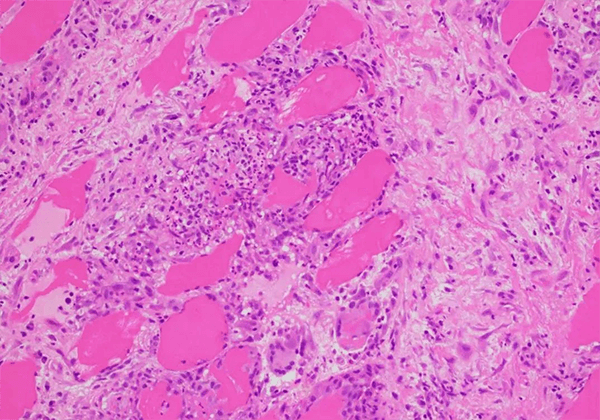

з»“иҠӮз—…жҳҜдёҖз§Қз—…еӣ дёҚжҳҺзҡ„ж…ўжҖ§еӨҡзі»з»ҹзӮҺжҖ§з–ҫз—…������пјҢзү№зӮ№дёәйқһе№Ій…Әж ·дёҠзҡ®ж ·иӮүиҠҪиӮҝ������пјҢдјҙжңүеҚ•дёӘж ёз»Ҷиғһжөёж¶Ұе’Ңеҫ®з»“жһ„зІүзўҺ���гҖӮиҜҘз—…еҸҜзҙҜеҸҠзҡ®иӮӨ������пјҢзңјзқӣ������пјҢеҝғи„Ҹе’ҢдёӯжһўзҘһз»Ҹзі»з»ҹ������пјҢи¶…иҝҮ90%зҡ„з—…дҫӢзҙҜеҸҠиӮәйғЁ���гҖӮиҜҘз–ҫз—…жҳҜжІүеӨ§зҡ„гҖҒжңӘж»Ўи¶ізҡ„еҢ»з–—йңҖиҰҒд№ӢдёҖ���гҖӮ

дҪңдёәйҖҡиҝҮFDAеӯӨе„ҝиҚҜиө„ж ји®Өе®ҡзҡ„ж–°иҚҜ������пјҢKBMAB-16жҳҜдёҖз§ҚеҲҶеӯҗйҮҸзәҰ149еҚғи·Ҝе°”йЎҝзҡ„дәәйј еөҢеҗҲжҠ—иӮҝзҳӨеқҸжӯ»еӣ еӯҗеҚ•е…ӢйҡҶжҠ—дҪ“������пјҢз”ЁдәҺеҢ»жІ»з»“иҠӮз—…дјҙжҲ–дёҚдјҙиӮәиЎЁеҸ—зҙҜзҡ„ж–°еһӢз”ҹзү©еҲ¶е“Ғ���гҖӮзӣ®еүҚе°ҡжңӘжңүеҢ»жІ»з»“иҠӮз—…зҡ„иӮҝзҳӨеқҸжӯ»еӣ еӯҗ-ОұжҠ‘йҖ еүӮиҺ·жү№������пјҢдҪҶKBMAB-16дҪңдёәиӮҝзҳӨеқҸжӯ»еӣ еӯҗ-ОұжҠ‘йҖ еүӮзҡ„зҗҶеҢ–жҖ§иҙЁе’ҢиҚҜзҗҶдҪңз”Ёе·ІиҝӣиЎҢдәҶеӨ§йҮҸй’»з ”���гҖӮ